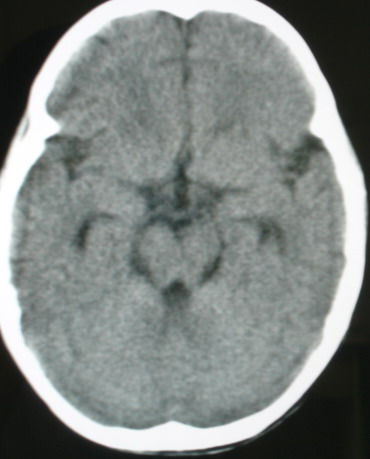

标题: PED0834:M8Y,考虑右侧海绵窦血管瘤 [打印本页]

标题: PED0834:M8Y,考虑右侧海绵窦血管瘤

m/8y,右侧眼睑下垂数天,头昏,无呕吐、无外伤史。无搏动性突眼。病人明天来增强。

考虑颈内动脉海绵窦段动脉瘤,建议mri检查。

考虑海绵窦血管瘤,做mri效果比较好。